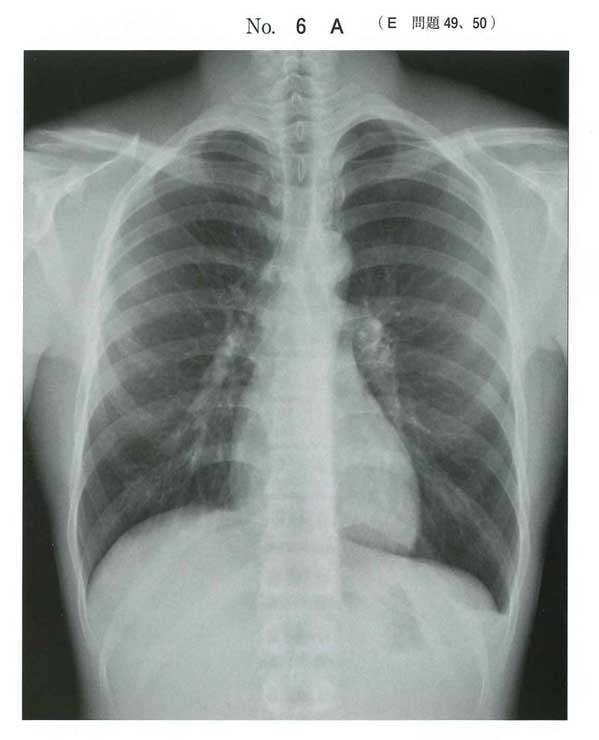

119D60(15問前!)では同じ気胸に対してドレナージを選ばせています。(外傷性であること、SpO2下がってて呼吸おかしくなる可能性高いからだとは思いますが。)

選択肢的にabdは気胸に治療ではない。eはやる可能性はあるにしてもドレナージして効果乏しければ実施。なのでドレナージか経過観察。

今回はそこまでひどい症状じゃないので経過観察かなと思いました。

>大きな変化は認められなかった

ここで大丈夫ですよアピールしていますね

c 外来で経過観察

実臨床では大きな変化がなければ外来で経過観察しています.疼痛あればカロナール等を処方しております.